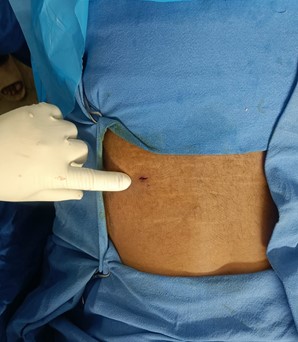

- Stitchless surgery or minimal stitches

- Minimal blood loss

- New day ambulation

- Same or next day discharge